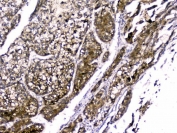

IHC staining of FFPE human liver cancer with RBP4 antibody. HIER: boil tissue sections in pH6, 10mM citrate buffer, for 20 min and allow to cool before testing.